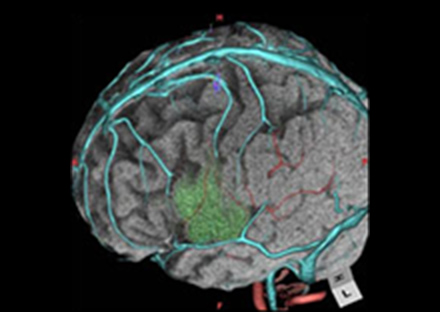

X線とコンピューターを利用して人体の断面画像を撮影する装置で、全身の臓器の形態診断に不可欠な存在となっています。当院のCT装置はエリアディテクターCTと呼ばれる最新の技術が用いられており、広範囲を短時間に撮影する事ができます。検出器1回転が0.275秒での超短時間ボリュームスキャンでスクリーニング検査から救急・精密検査まで、一度の撮影で多くの情報を得ることが可能です。得られた画像から脳血管や心臓血管・骨などの立体的(三次元)表示・解析も可能となっております。また、造影剤を使用することで、より詳しい検査を行う事も可能です。

3D医用画像処理ワークステーション ziostation2

画像提供:アミン株式会社